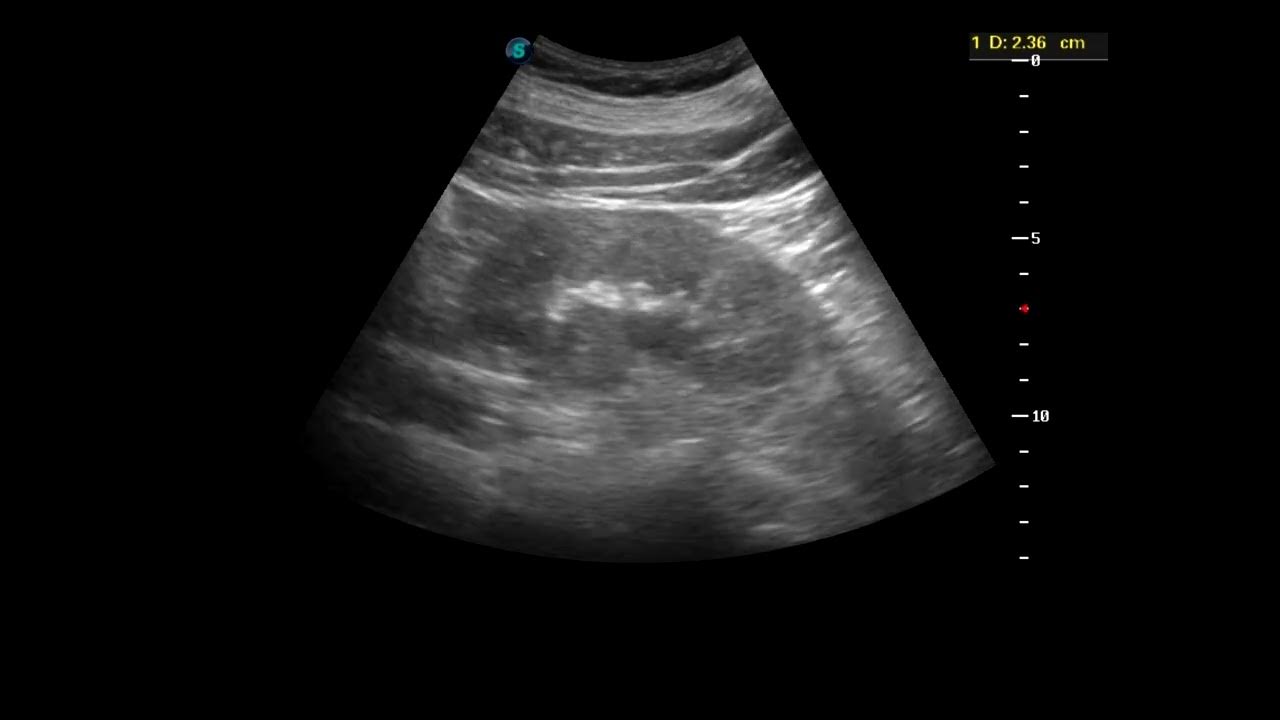

УЗИ почек: диагностика туберкулеза и рекомендации